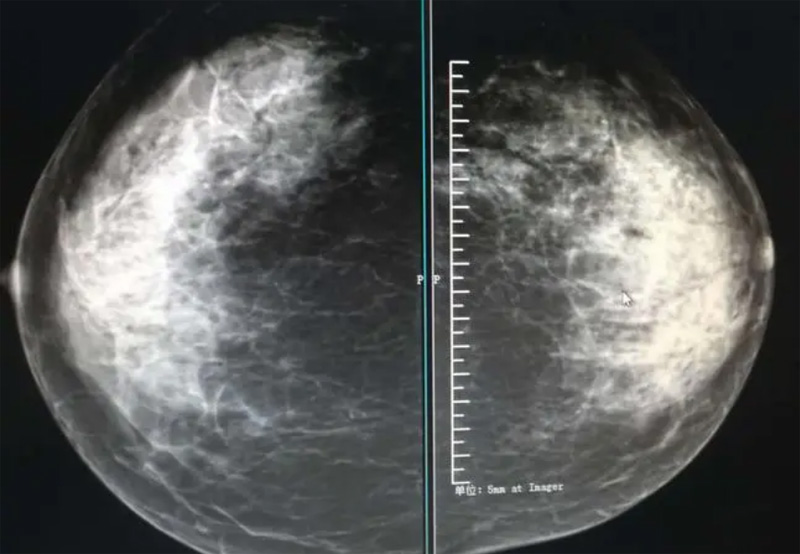

乳腺DR攝影體位有頭尾位及內外側斜位,

乳房在片子的中央,乳頭切線位,可見小部分胸大肌,內側乳腺組織應全部包括在片中,外側乳腺組織盡可能包括在片中。一張好的MLO位圖像顯示如下:乳房被推向前上,乳腺實質充分展開,胸大肌可見,較松弛,下緣達到乳頭水平,乳頭在切線位,部分腹壁包括在片中,但與下部乳腺分開,絕大部分乳腺實質顯示在片中。乳腺組織外緣可見乳頭的輪廓;乳腺后方的脂肪組織被很好地顯示出來,乳房無皺褶。對于CC位及MLO位顯示不良或未包全的乳腺實質,可以根據病灶位置的不同選擇以下體位:外內側位(LM)、內外側位(ML)、內側頭尾軸位(MCC)、外側頭尾軸位(LCC),尾葉位(CLEO)及乳溝位。在臨床實踐中,對于常規體位上發現的異常改變,可以進一步采取一些特殊的攝影技術,包括局部加壓攝影、放大攝影或局部加壓放大攝影技術。